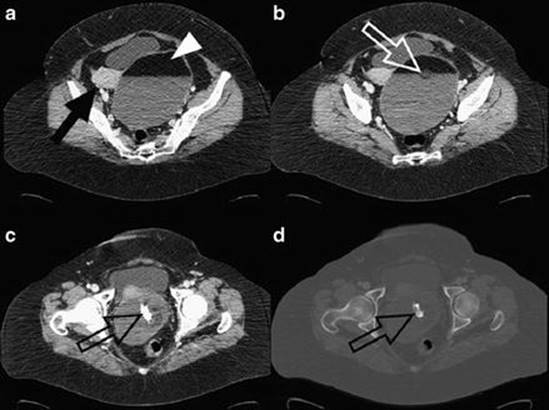

Fig. 4.7

Ovarian teratoma. Contrast-enhanced CT scan (a, b) shows well-defined ovarian tumor with fat-fluid level (white arrowhead), round mass of matted tuft of hair (white open arrow), and enhancing lobulated soft-tissue component (black arrow) in lateral wall. A toothlike calcification in inferior wall is visible (black open arrow) in (c, d) scans (Reprinted from Saba et al. [59], with permission from Elsevier)